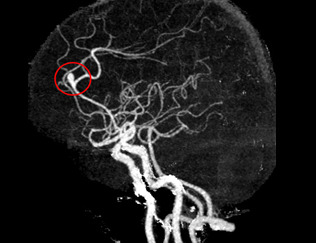

뇌동맥류를 정확하게 진단하기 위해서는 뇌혈관의 상태를 상세히 확인할 수 있는 검사가 필요합니다. 그 중 하나가 뇌혈관 조영술입니다.

뇌혈관 조영술은 대퇴동맥을 통해 카테터라는 2mm 내외의 관을 삽입한 후 조영제를 주입하고 X-ray를 촬영하여 뇌혈관의 상태를 파악하는 검사입니다. 이 검사는 뇌동맥류, 뇌혈관 협착, 뇌동정맥 기형 등의 진단에 매우 정확하며, 치료 계획을 세우는 데 필수적입니다.